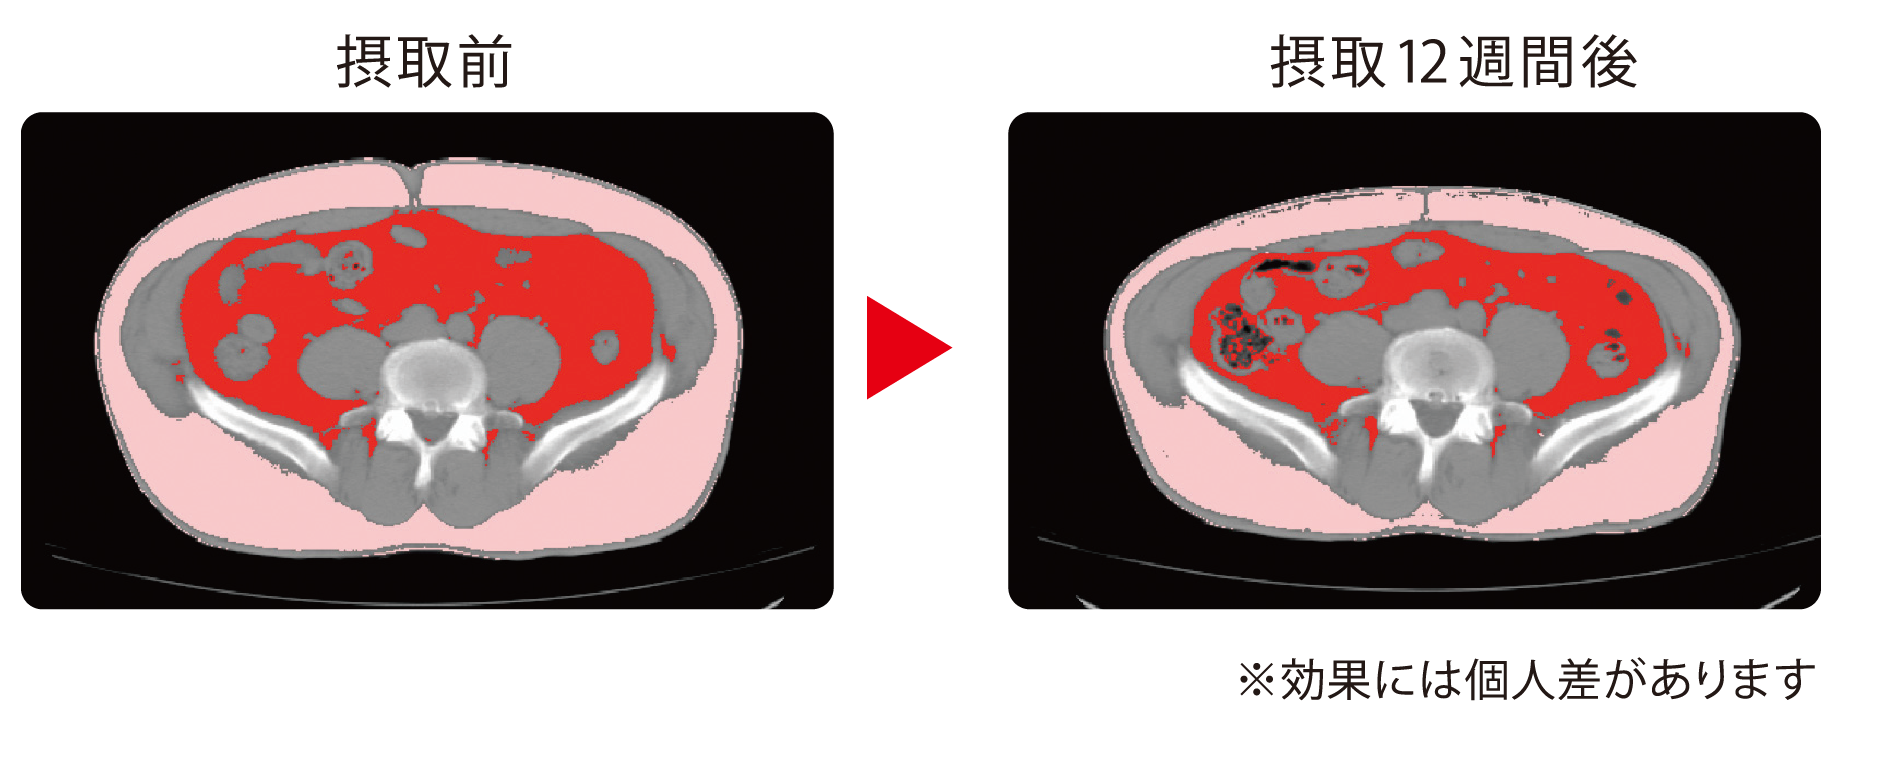

肥満傾向(BMI値: 25kg/㎡以上30kg/㎡未満、内臓脂肪面積: 80㎠以上)の20歳以上65歳未満の成人被験者101名( 「ガセリ菌SP株」入りヨーグルト群: 52名、プラセボヨーグルト群: 49名)を対象に二重盲検並行群間比較試験を実施した。被験者は、 「ガセリ菌SP株」入りヨーグルト1OOg( 「ガセリ菌 SP株」10億個)を摂取した群(男性: 27名、女性: 25名)、および 「ガセリ菌SP株」を含まないプラセボヨーグルト100gを摂取した群(男性: 27名、女性: 22名)の2群に分け、それぞれのヨーグルトを1日1個、12週間毎日摂取した。※プラセボヨーグルトは、 「ガセリ菌SP株」を含まないヨーグルトです。

出典 高野義彦(雪印メグミルク(株))ほか 薬理と治療,41,895-903,2013

「ガセリ菌SP株」を用いた実験結果(研究レビューの対象となった論文のうち、代表的な一報を事例として提示しています。)

腹部断面画像は、論文内で示した内臓脂肪面積に関する測定結果の一例です。

ヒト試験のCTスキャン測定で得られた被験者の腹部断面画像(赤色:内臓脂肪)